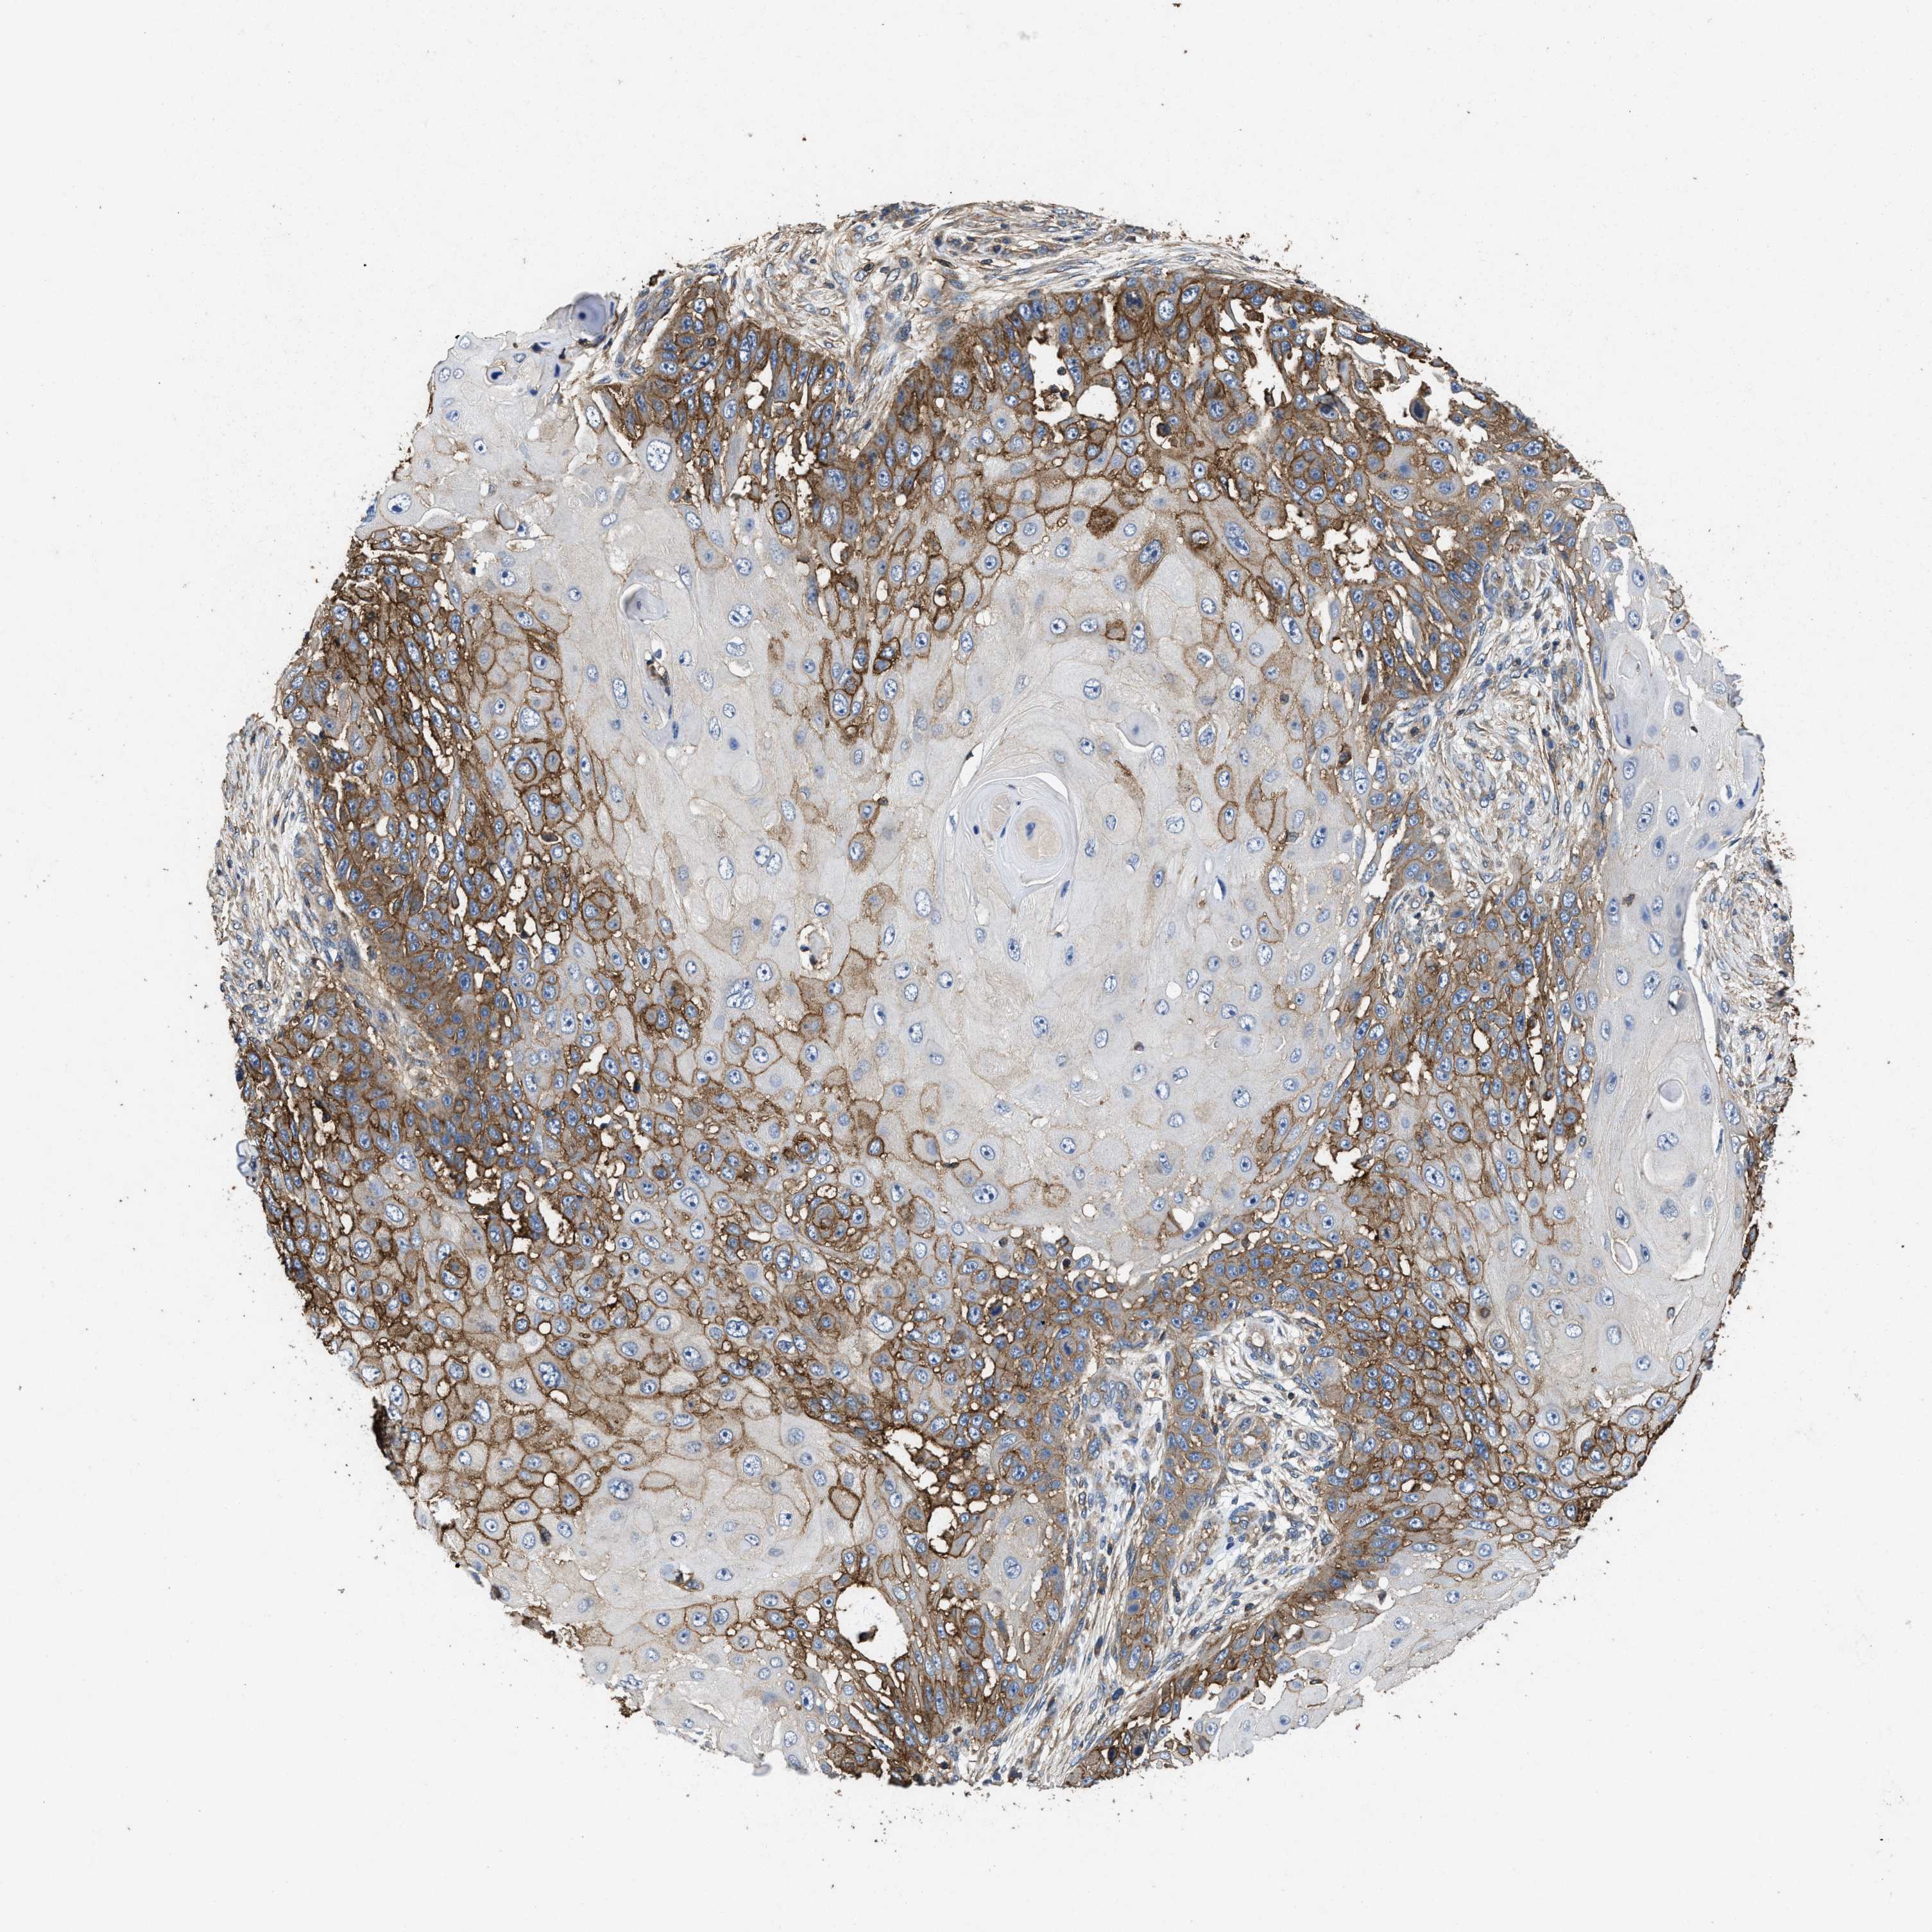

SKIN CANCER - Protein expressioni

A mouse-over function shows sample information and annotation data. Click on an image to view it in a full screen mode. Samples can be filtered based on level of antibody staining by selecting one or several of the following categories: high, medium, low and not detected. The assay and annotation is described here.

Antibody stainingi

Antibody staining in the annotated cell types in the current human tissue is reported as not detected, low, medium, or high, based on conventional immunohistochemistry profiling in selected tissues. This score is based on the combination of the staining intensity and fraction of stained cells.

Each image is clickable and will lead to virtual microscopy that enables deeper exploration of all samples and also displays staining intensity scores, fraction scores and subcellular localization as well as patient and tissue information for each sample.

Antibody HPA016633

High

Intensity

Quantity

Location

Squamous cell carcinoma in situ, NOS